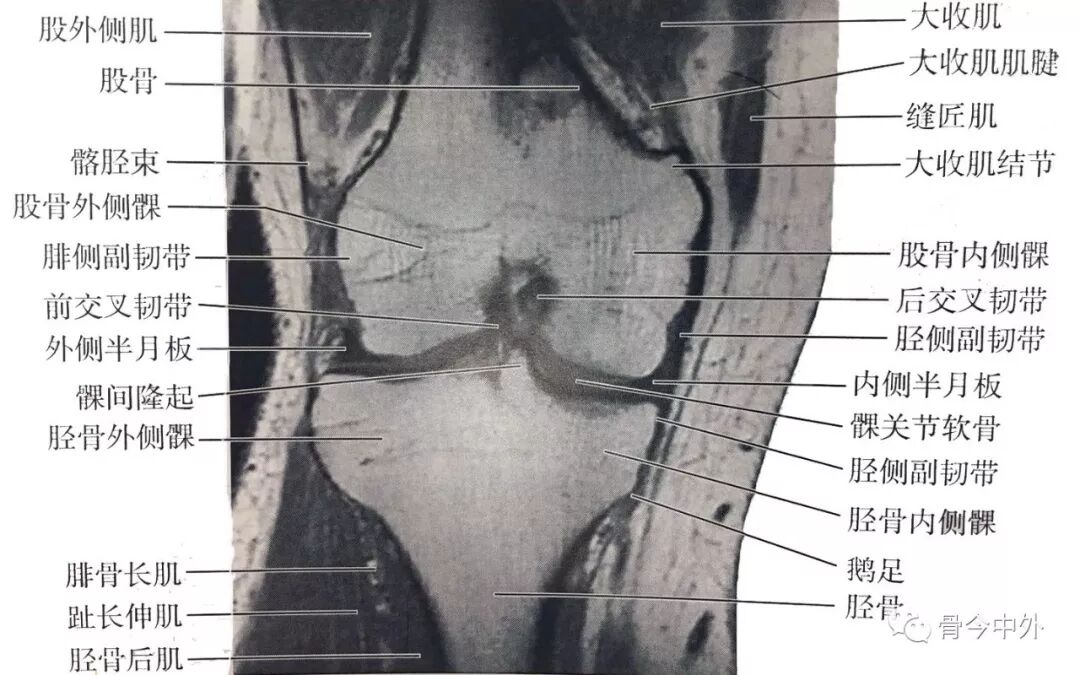

(2)膝中部冠状断层:该层面解剖关系结构如图

膝中部冠状断层